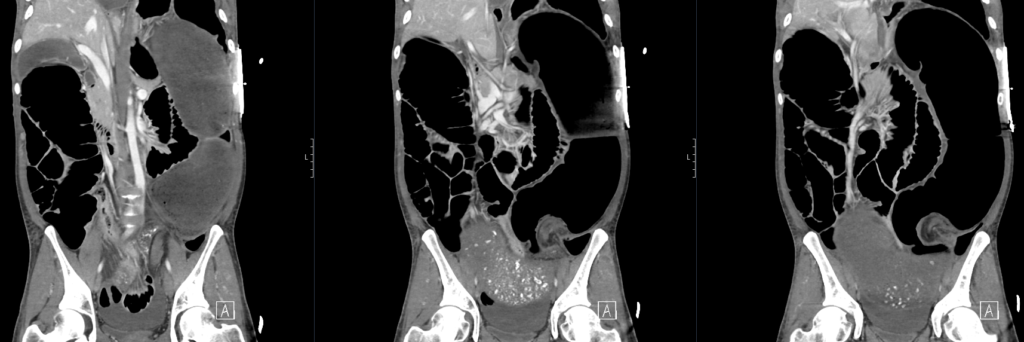

CT mesenteric angiogram

There is evidence of a sigmoid volvulus.

The proximal large bowel as well as small bowel loops are dilated suggestive of an incompetent ileocaecal valve.

There is no pneumoperitoneum to suggest hollow viscus perforation.

There is a moderate volume of free fluid. No collection.

The distended bowel compresses the liver and displaces the gallbladder and spleen posteriorly.

The abdominal aorta as well as the origins of the common iliac arteries and external iliac arteries are compressed by dilated bowel loops however remain patent and there is satisfactory flow distally to the common femoral and superficial femoral arteries.

There is narrowing of the proximal coeliac trunk likely due to compression by the median arcuate ligament. The coeliac trunk and its major branches are otherwise patent. The SMA and IMA are patent.

The distal oesophagus is distended.

The visualised lung bases are clear. No pleural effusions.

Comment: Acute sigmoid volvulus with severe bowel obstruction. The dilated bowel loops are significantly compressing the abdominal aorta and pelvic arteries as above. Urgent surgical review recommended.